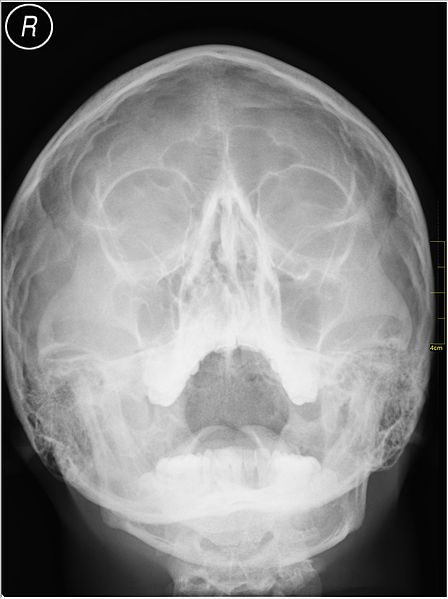

SCP-7380的X射线成像,在